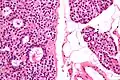

Микропрепарат аденомы паращитовидной железы.

Микропрепарат аденомы паращитовидной железы. Микропрепарат аденомы паращитовидной железы.

Микропрепарат аденомы паращитовидной железы..jpg) Микропрепарат аденомы паращитовидной железы.

Микропрепарат аденомы паращитовидной железы..jpg) Микропрепарат аденомы паращитовидной железы.

Микропрепарат аденомы паращитовидной железы..jpg) Микропрепарат аденомы паращитовидной железы.

Микропрепарат аденомы паращитовидной железы.